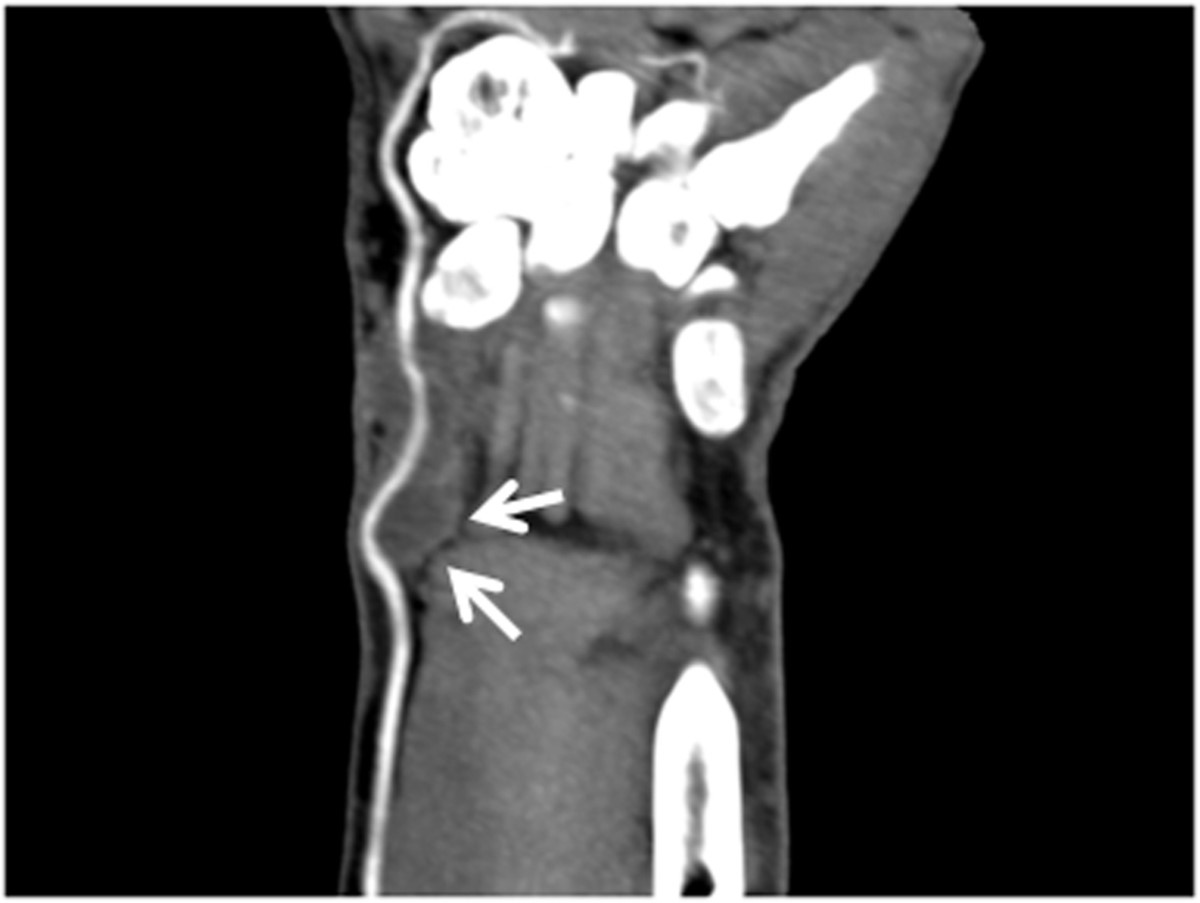

Fig. 2.

Fig. 2. CT angiogram of the left wrist shows tortuous but patent radial artery and a 1.0x3.0cm pseudoaneurysm with thrombus formation surrounding left radial artery.